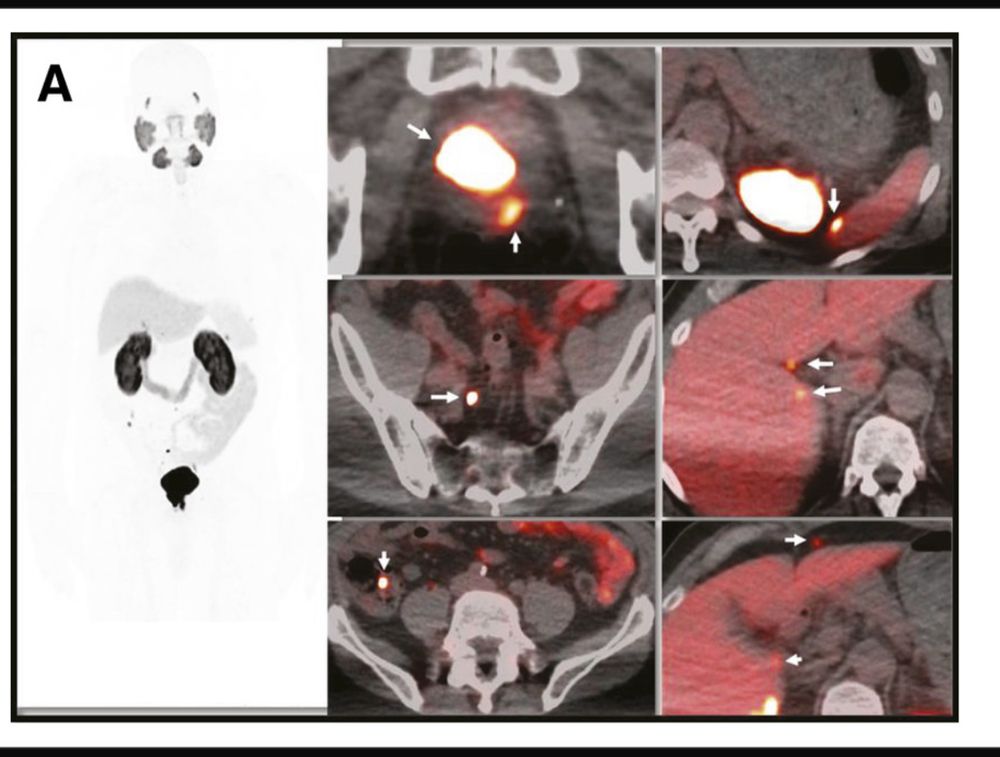

73 yo male PSA=17 PSADT=11.6mos

PSMA=5+ nodes in pelvis RP & torso

(All~5mm). Neg CT and bone scan

No🚫Treatment

1 yr later

PSA=40 PSADT=13.1 mos

PSMA stable across 2 scans over 12 mos

#PSMA+ #BCR #ProstateCancer is an indolent process-OK to monitor these pts